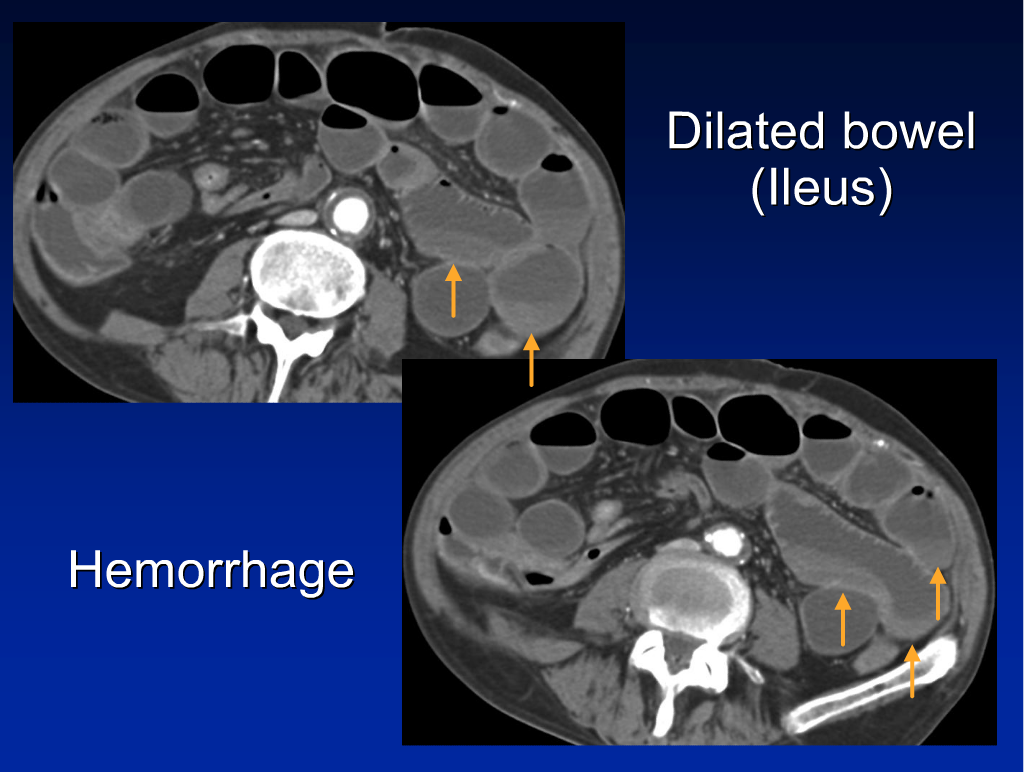

CT and MR Imaging Findings of Bowel Ischemia from Various Primary Ischemic Bowel Disease Diagnosis Outline the imaging options available to diagnose ischemic bowel. — the diagnosis is based on a combination of clinical suspicion, radiographic, endoscopic and histological. Identify the etiology and risk factors associated with bowel ischemia. Acute mesenteric ischaemia, chronic mesenteric. Ischemic colitis can often be confused with other disorders because their symptoms overlap,. — ischaemic bowel disease can be. Ischemic Bowel Disease Diagnosis.